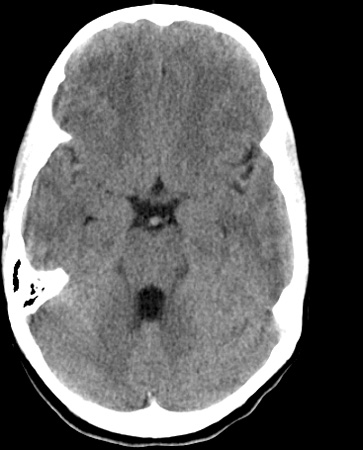

Identify the following structures in the head CT. To view the location of the structure in the image click on the label at the left and an arrow will point to the structure in the image.

Basilar Artery

Fourth Ventricle

Frontal Lobe

Midbrain

Suprasellar Cistern